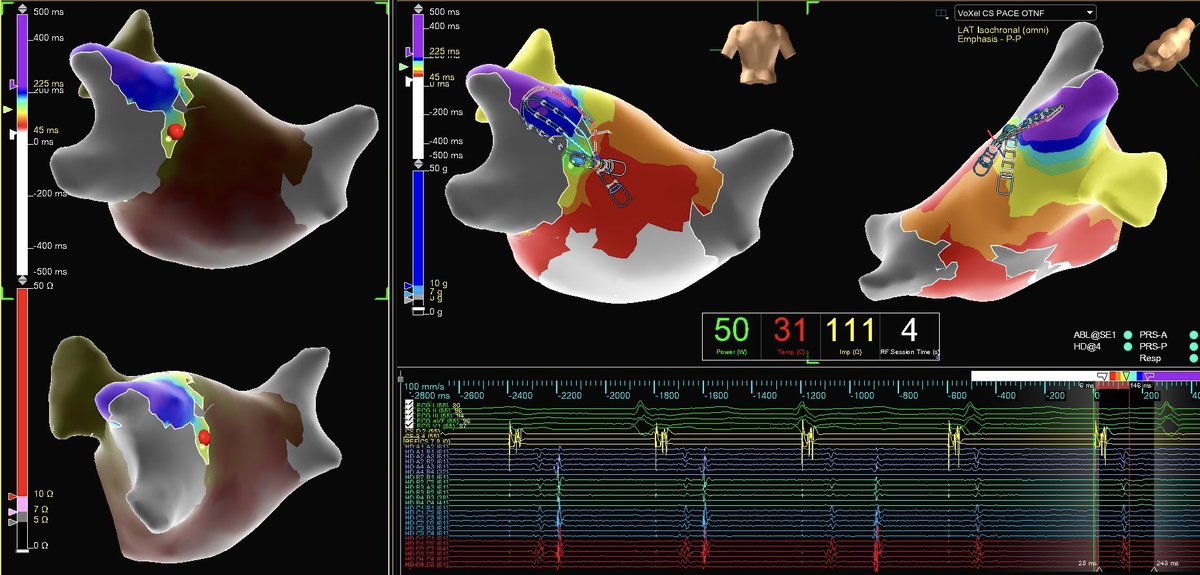

Redo AF/AFL ablation with #EnsiteX. Typical CCW Atrial Flutter was induced and mapped with #HDGrid. Look at how conduction jumps epicardially over the already twice ablated CTI - the #OT arrows confirm by pointing back at the line from the breakout. #ProudToBeAbbott #MidAmericaEP